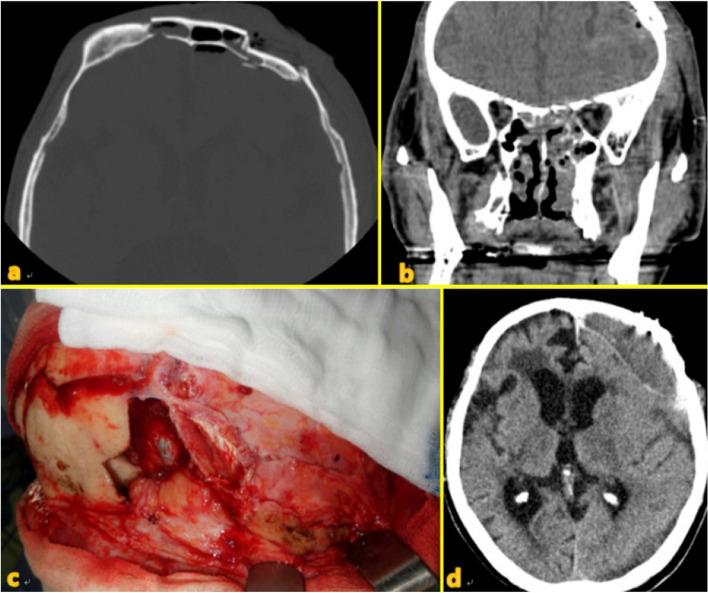

Frontal sinus injuries are relatively rare among facial bone traumas. Without proper treatment, they can lead to fatal intracranial complications, including meningitis or brain abscesses, as well as aesthetic and functional sequelae. The management of frontal sinus injuries remains controversial, with various treatment methods and outcomes being reported. This article describes the clinical characteristics, surgical methods, and outcomes among 17 patients who underwent surgery for frontal sinus injury and related complications.

We retrospectively included 17 patients who underwent surgery for frontal sinus injury and its related complications at the Kangwon National University Hospital between July 2010 and September 2021. Among them, six underwent simple open reduction and fixation of the anterior wall, eight underwent sinus obliteration, and three underwent cranialization. Two patients who underwent sinus obliteration died due to infection-related complications. The patient who underwent cranialization reported experiencing chronic headache and expressed dissatisfaction regarding the esthetic outcomes of the forehead. Except for these three patients, the other patients achieved satisfactory esthetic and functional recovery.